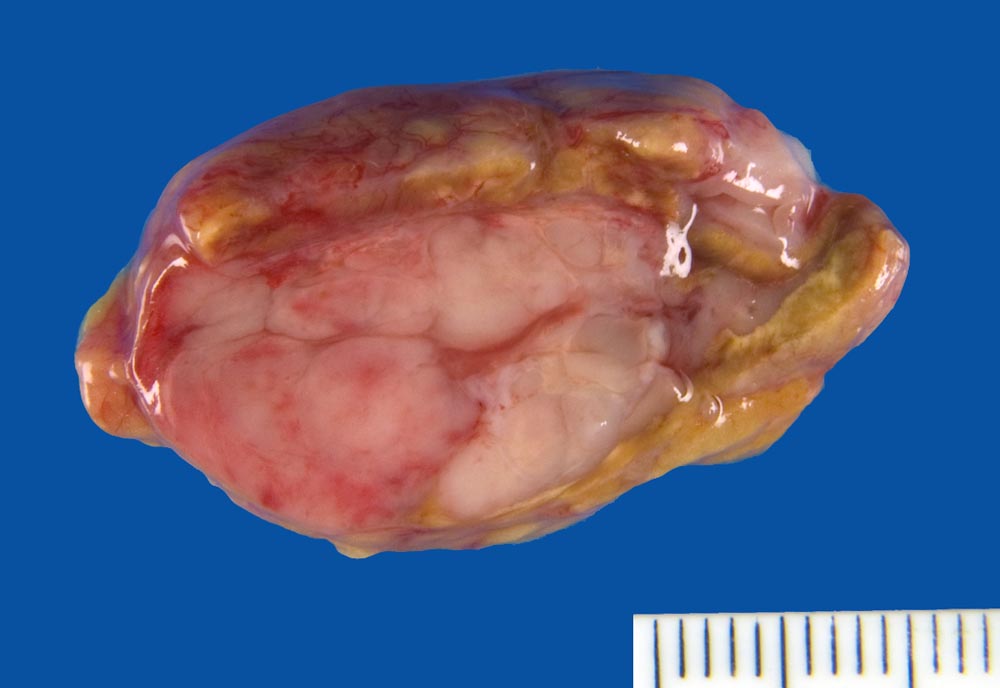

Infiltrate eines Plasmazellmyeloms in der Nebenniere

Knotige weisse Tumorinfiltrate in der Nebenniere.